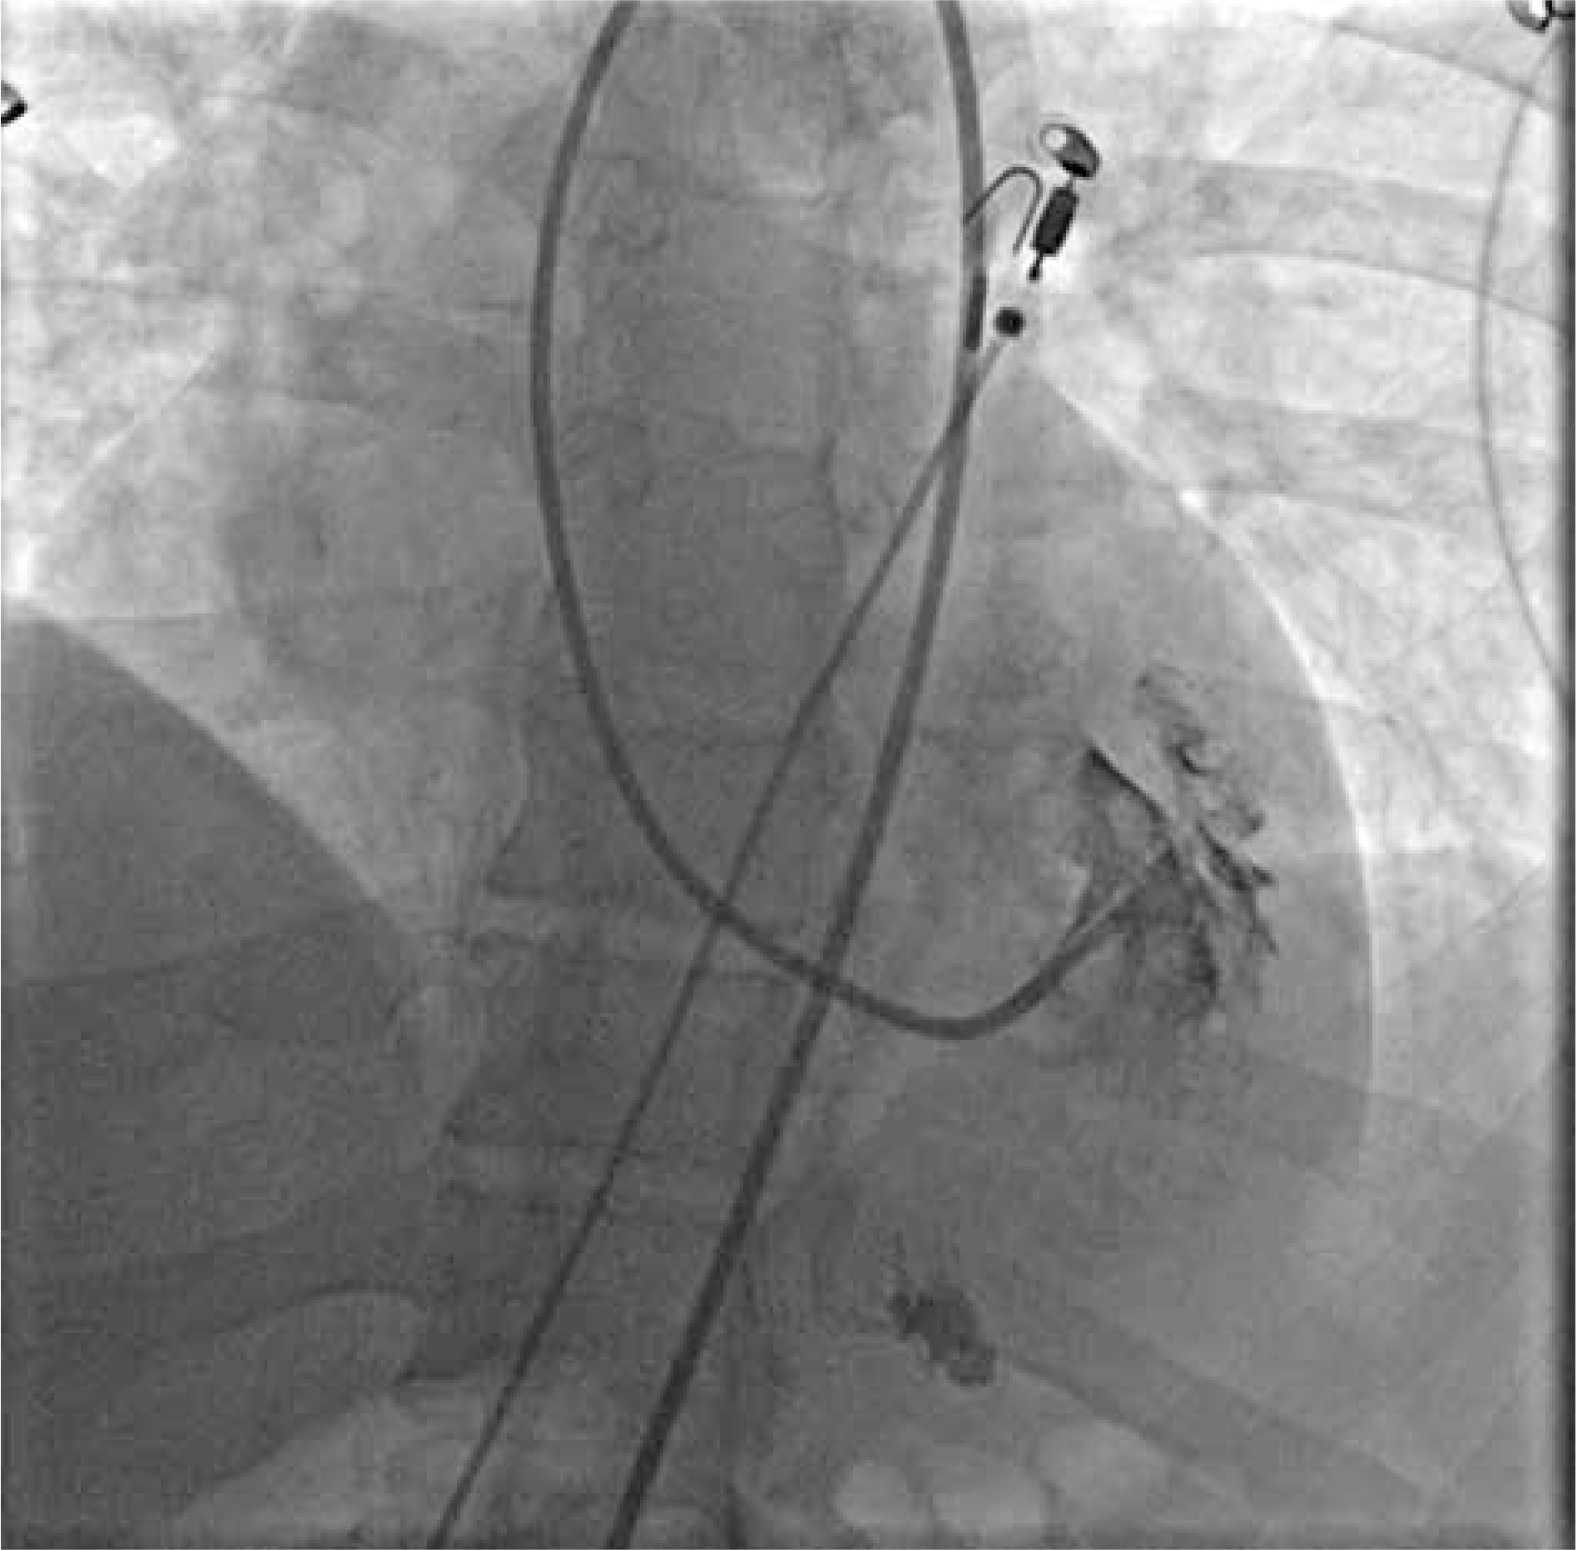

The optimal position and distance between the tip of the guiding catheter and the lateral wall of the LV were checked in the left oblique 20° projection by injecting 5–6 ml of contrast medium. The tip of the catheter should optimally point to the left at the free (lateral) wall of the LV, but it should not touch it (Figure 2). After checking the location of the catheter, 104 cm long Cordis (USA) 5.5 F biopsy forceps were inserted under fluoroscopy guidance near the tip of the guiding catheter. Afterwards, they were opened while still inside the guide catheter and carefully moved toward the lateral wall of the LV (Figure 3). After taking the sample, the closed biopsy forceps were withdrawn slowly into the guide catheter under fluoroscopy control. In total, 6–9 biopsy specimens of 1–2 mm in size with a material volume of approximately 2.4 mm2 were taken from different sites of the LV. To avoid air embolism, before each insertion of the bioptome into the catheter, the forceps were thoroughly rinsed with saline solution.

Figure 3

Collection of left ventricular specimens. Bioptome touches the free (lateral) wall of the left ventricle